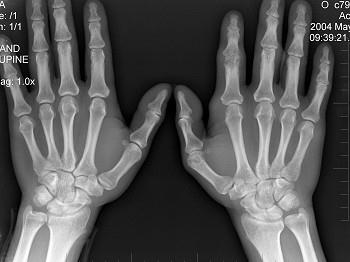

男,19岁,双手肿痛2年,晨僵,结合图像,最可能诊断是?(?)A.痛风B.强直性脊柱炎C.类风湿关节炎D.退行性关节炎E.未见异常

问题 男,19岁,双手肿痛2年,晨僵,结合图像,最可能诊断是?(?)

选项 A.痛风 B.强直性脊柱炎 C.类风湿关节炎 D.退行性关节炎 E.未见异常

答案 C